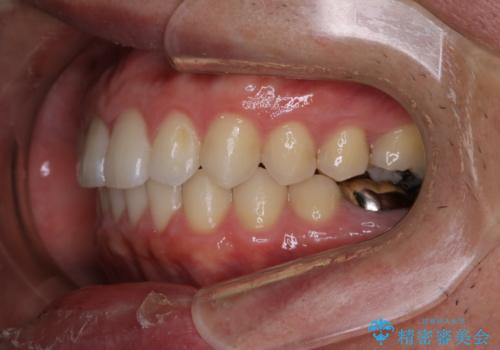

- 全体的に歯と歯の間に隙間があるのが気になるとのことで来院されました。インビザラインでの矯正治療をご希望されました。

隙間については、前歯と奥歯に多数あります。また、上下前歯は、外側に少し倒れているため隙間を閉じつつ、前歯を内側に引っ込めて並べることになりました。

インビザライン・ライトにて矯正治療を行うことになりました。